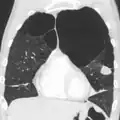

A CT scan is not routinely used except for the exclusion of bronchiectasis.[5] An analysis of arterial blood is used to determine the need for oxygen supplementation and assess for high levels of carbon dioxide in the blood; this is recommended in those with an FEV1 less than 35% predicted, those with a peripheral oxygen saturation less than 92% and those with symptoms of congestive heart failure.[118] WHO recommends that all those diagnosed with COPD be screened for alpha-1 antitrypsin deficiency.[45]

A severe case of bullous emphysema

Axial CT image of the lung of a person with end-stage bullous emphysema